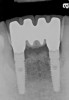

Preoperatively, 1 g of amoxicillin was administered. Using local anesthesia (lidocaine 1:100,000 epinephrine), extractions of teeth No. 23 to No. 26 were performed without raising a flap and with gentle luxation to preserve the remaining facial osseous plate. The sockets were curetted prior to implant placement. A vacuum-formed surgical guide, fabricated based on a diagnostic wax-up of the desired tooth positions for the subsequent fixed prosthesis, was used during implant placement. Osteotomies were performed at sites No. 23 and No. 26 and positioned toward the lingual aspects of the sockets (Figure 3A and Figure 3B). Two tapered implants (OsseoTite™ 313, BIOMET 3i™, Palm Beach Gardens, FL) measuring 3.25 mm x 13 mm were placed. Conical prosthetic abutments (3-mm height) were used to facilitate joining the two implants in a screw-retained fixed partial denture (Figure 4). A laboratory-processed acrylic-resin provisional restoration was altered to allow connection to the temporary cylinders. The provisional was placed into the vacuum-formed surgical guide that was now used to maintain the provisional in the correct 3-dimensional position (Figure 5) while being attached to the temporary cylinders with acrylic resin intraorally. Once a sufficient amount of acrylic resin was placed to secure the cylinders to the provisional, it was removed from the mouth and its contours were completed at the laboratory bench (Figure 6A). The two central incisor sockets were grafted with small-particle allograft material (Puros® Allograft, Zimmer Dental, Carlsbad, CA) to maintain gingival architecture beneath two ovate pontics (Figure 6B). The provisional restoration was inserted and the screws tightened to 20 Nt-cm of torque.

The patient was given postoperative instructions and advised to maintain a soft diet for 6 to 8 weeks to protect the implants. The patient was followed weekly for the first 3 weeks and monthly thereafter. After 4 months of healing, the provisional restoration was removed and the soft tissues were examined. Mature, keratinized gingival tissues were present facially, lingually, and interproximally. Nonkeratinized tissue could be seen at the tissue surfaces of the ovate pontics and in the intrasulcular regions of the implant abutment units. No clinical probing depths beyond 1 mm were found adjacent to the abutments. The healed tissue represented an acceptable clinical result especially in light of the gap that had been present at the time of implant placement (Figure 7A and Figure 7B). Final impressions were made, and the permanent ceramo-metal screw-retained prosthesis was placed within 8 weeks (Figure 8).